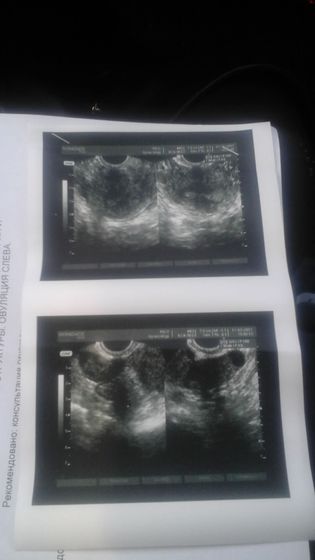

В сентябре 2015 года мне делали операцию гистерорезектоскопию, убирали спайки в матке, прошло 1,5 с тех пор, сделала в субботу узи, а там опять одна спайка выросла как перемычка от стенки до стенки, что с ней делать незнаю, столько всего сделано и выпито и опять всё сначало ((((((

Боюсь что спайка мешает, и что еще спайки появятся

С трубами у меня тьфу, тьфу, тьфу всё впорядке, а вот это спайка мне покоя недаёт....